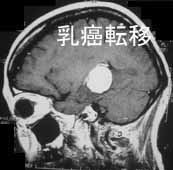

代表例の提示

転移性脳腫瘍 肺癌の脳内転移

[ラジオサージャリー前]

CT(左画像): 左下の黒くなっているところが癌、 造影MR(右画像):左下の周りが白い線で囲まれたようになっているところが癌

[ラジオサージャリー後2ヵ月半]

CT、MRともに癌が縮小している。